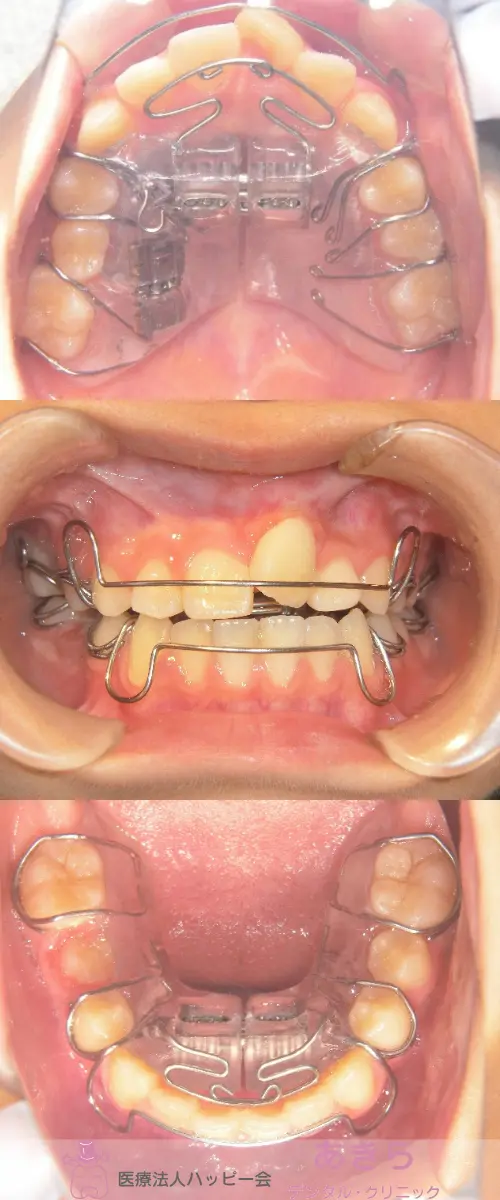

2021年5月8日 口腔内写真(経過時)

2019年4月9日 初診時 ⇒ 2021年5月8日 口腔内写真(経過時)

- 2019年11月末より SHA(SH装置)スタート

- SHA修理 下顎1回

- 2021年5月 SHA休止